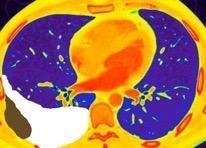

Hemorrágica………….30-70 UH

Extravasación iv. con sangrado activo……….>90 UH

“Simpático”………….,,,,<15 UH

Durso AM et al. Penetrating Thoracic Injury. Radiol Clin N Am 2015.

Urogénico……………….< 15 UH

Entérico.. ………………+/- 15UH

Biliar, Quiloso……………..<0 UH

Abramowitz1 Y et al. Pleural Effusion: Characterization with CT Attenuation Values and CT Appearance .AJR 2008